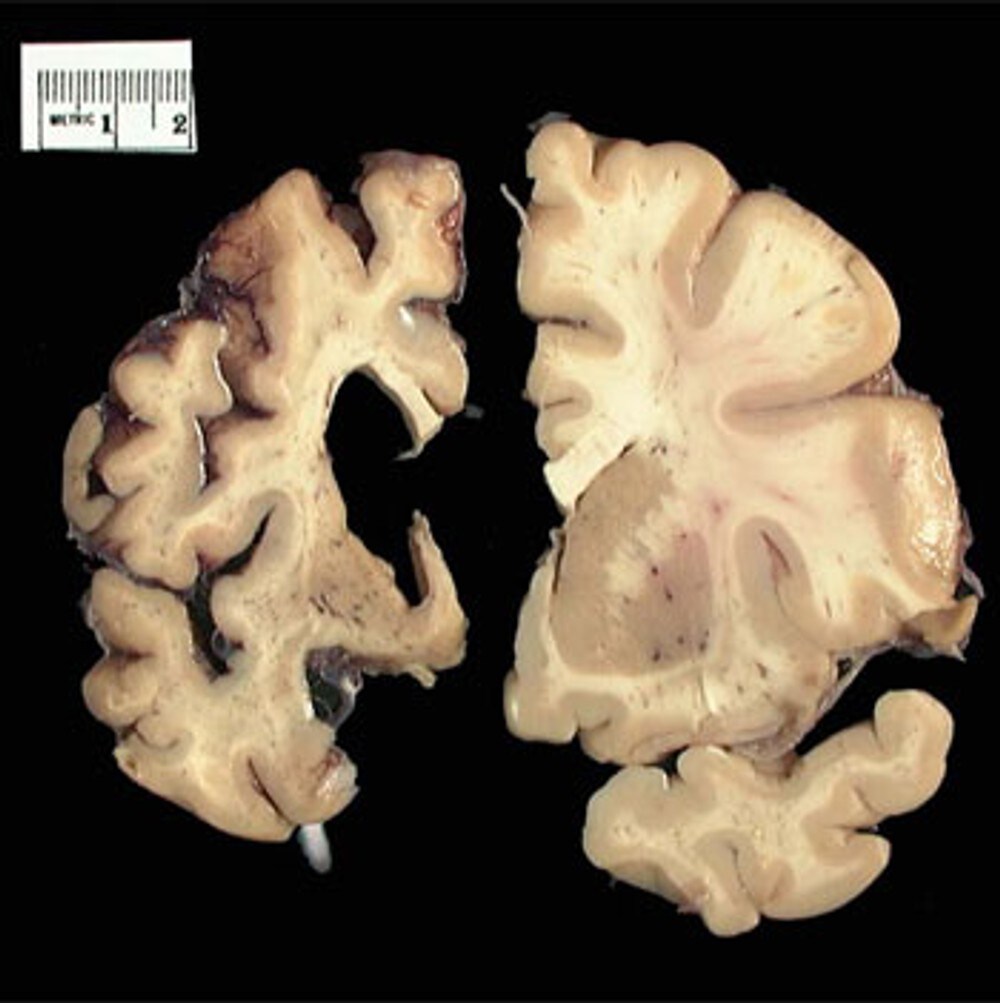

Болезнь (или синдром, или хорея) Хантингтона (Huntington Disease) — это генетическое заболевание нервной системы, характеризующееся постепенным началом обычно в возрасте 35-50 лет и сочетанием прогрессирующего хореического гиперкинеза и психических расстройств. Заболевание вызывается умножением кодона CAG в гене IT-15. Этот ген кодирует 350-kDa белок хантингтин с неизвестной функцией. В гене дикого типа (не мутантного) у разных людей присутствует разное количество CAG повторов, однако, когда число повторов превышает 36, развивается болезнь. Нейроморфологическая картина характеризуется атрофией стриатумa, а на поздней стадии также атрофией кортекса.

Определённые функции головного мозга, такие как контроль движений, мышление и речь, при БГ постепенно нарушаются, т.к. ответственные за них нервные клетки повреждаются и гибнут. Часть головного мозга, которая страдает в наибольшей степени при БГ, носит название полосатое тело и является частью так называемых базальных ядер — структур, расположенных глубоко в центральной части головного мозга. В первую очередь, полосатое тело отвечает за планирование и контроль движений, но оно также обеспечивает и многие другие процессы, включая мышление и эмоции. По мере прогрессирования БГ повреждается и кора головного мозга (наиболее поверхностно расположенная его часть, имеющая извилины), что усугубляет выраженность когнитивных нарушений.

В целом, с течением времени БГ приводит к атрофии всего головного мозга, приводя к общей инвалидизации человека.